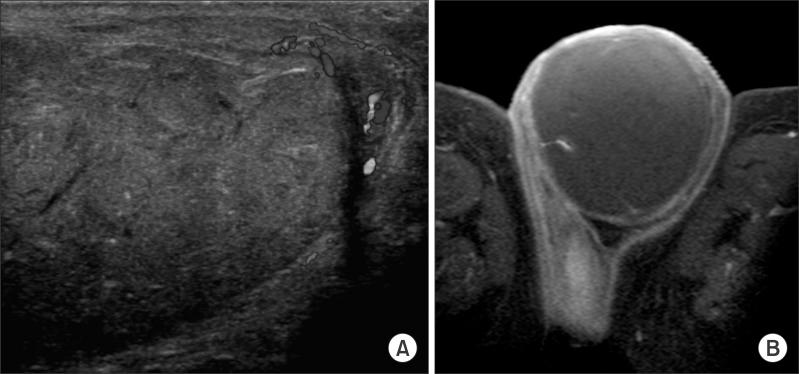

The Testis Completely Replaced by a Huge Epidermal Cyst in an Older Man.

Epidermal cysts are commonly encountered, slow-growing superficial cysts in the hair-bearing areas of the body, and are usually discovered in the second and fourth decades of life. These cysts tend to be superficial, meaning that they can be easily found by ultrasound and digital palpation at a moderate degree of growth. However, we found a huge testicular cyst that went undetected until old age. In this report, we describe the interesting case of a patient in whom the right testis was totally replaced with an epidermal cyst. The cyst was found by ultrasonography and further evaluated with magnetic resonance imaging. We performed orchiectomy under the impression of an epidermal cyst. The pathologic report confirmed this clinical impression. Over 24 months of follow-up, we did not find any recurrence of a growing mass on the testis.